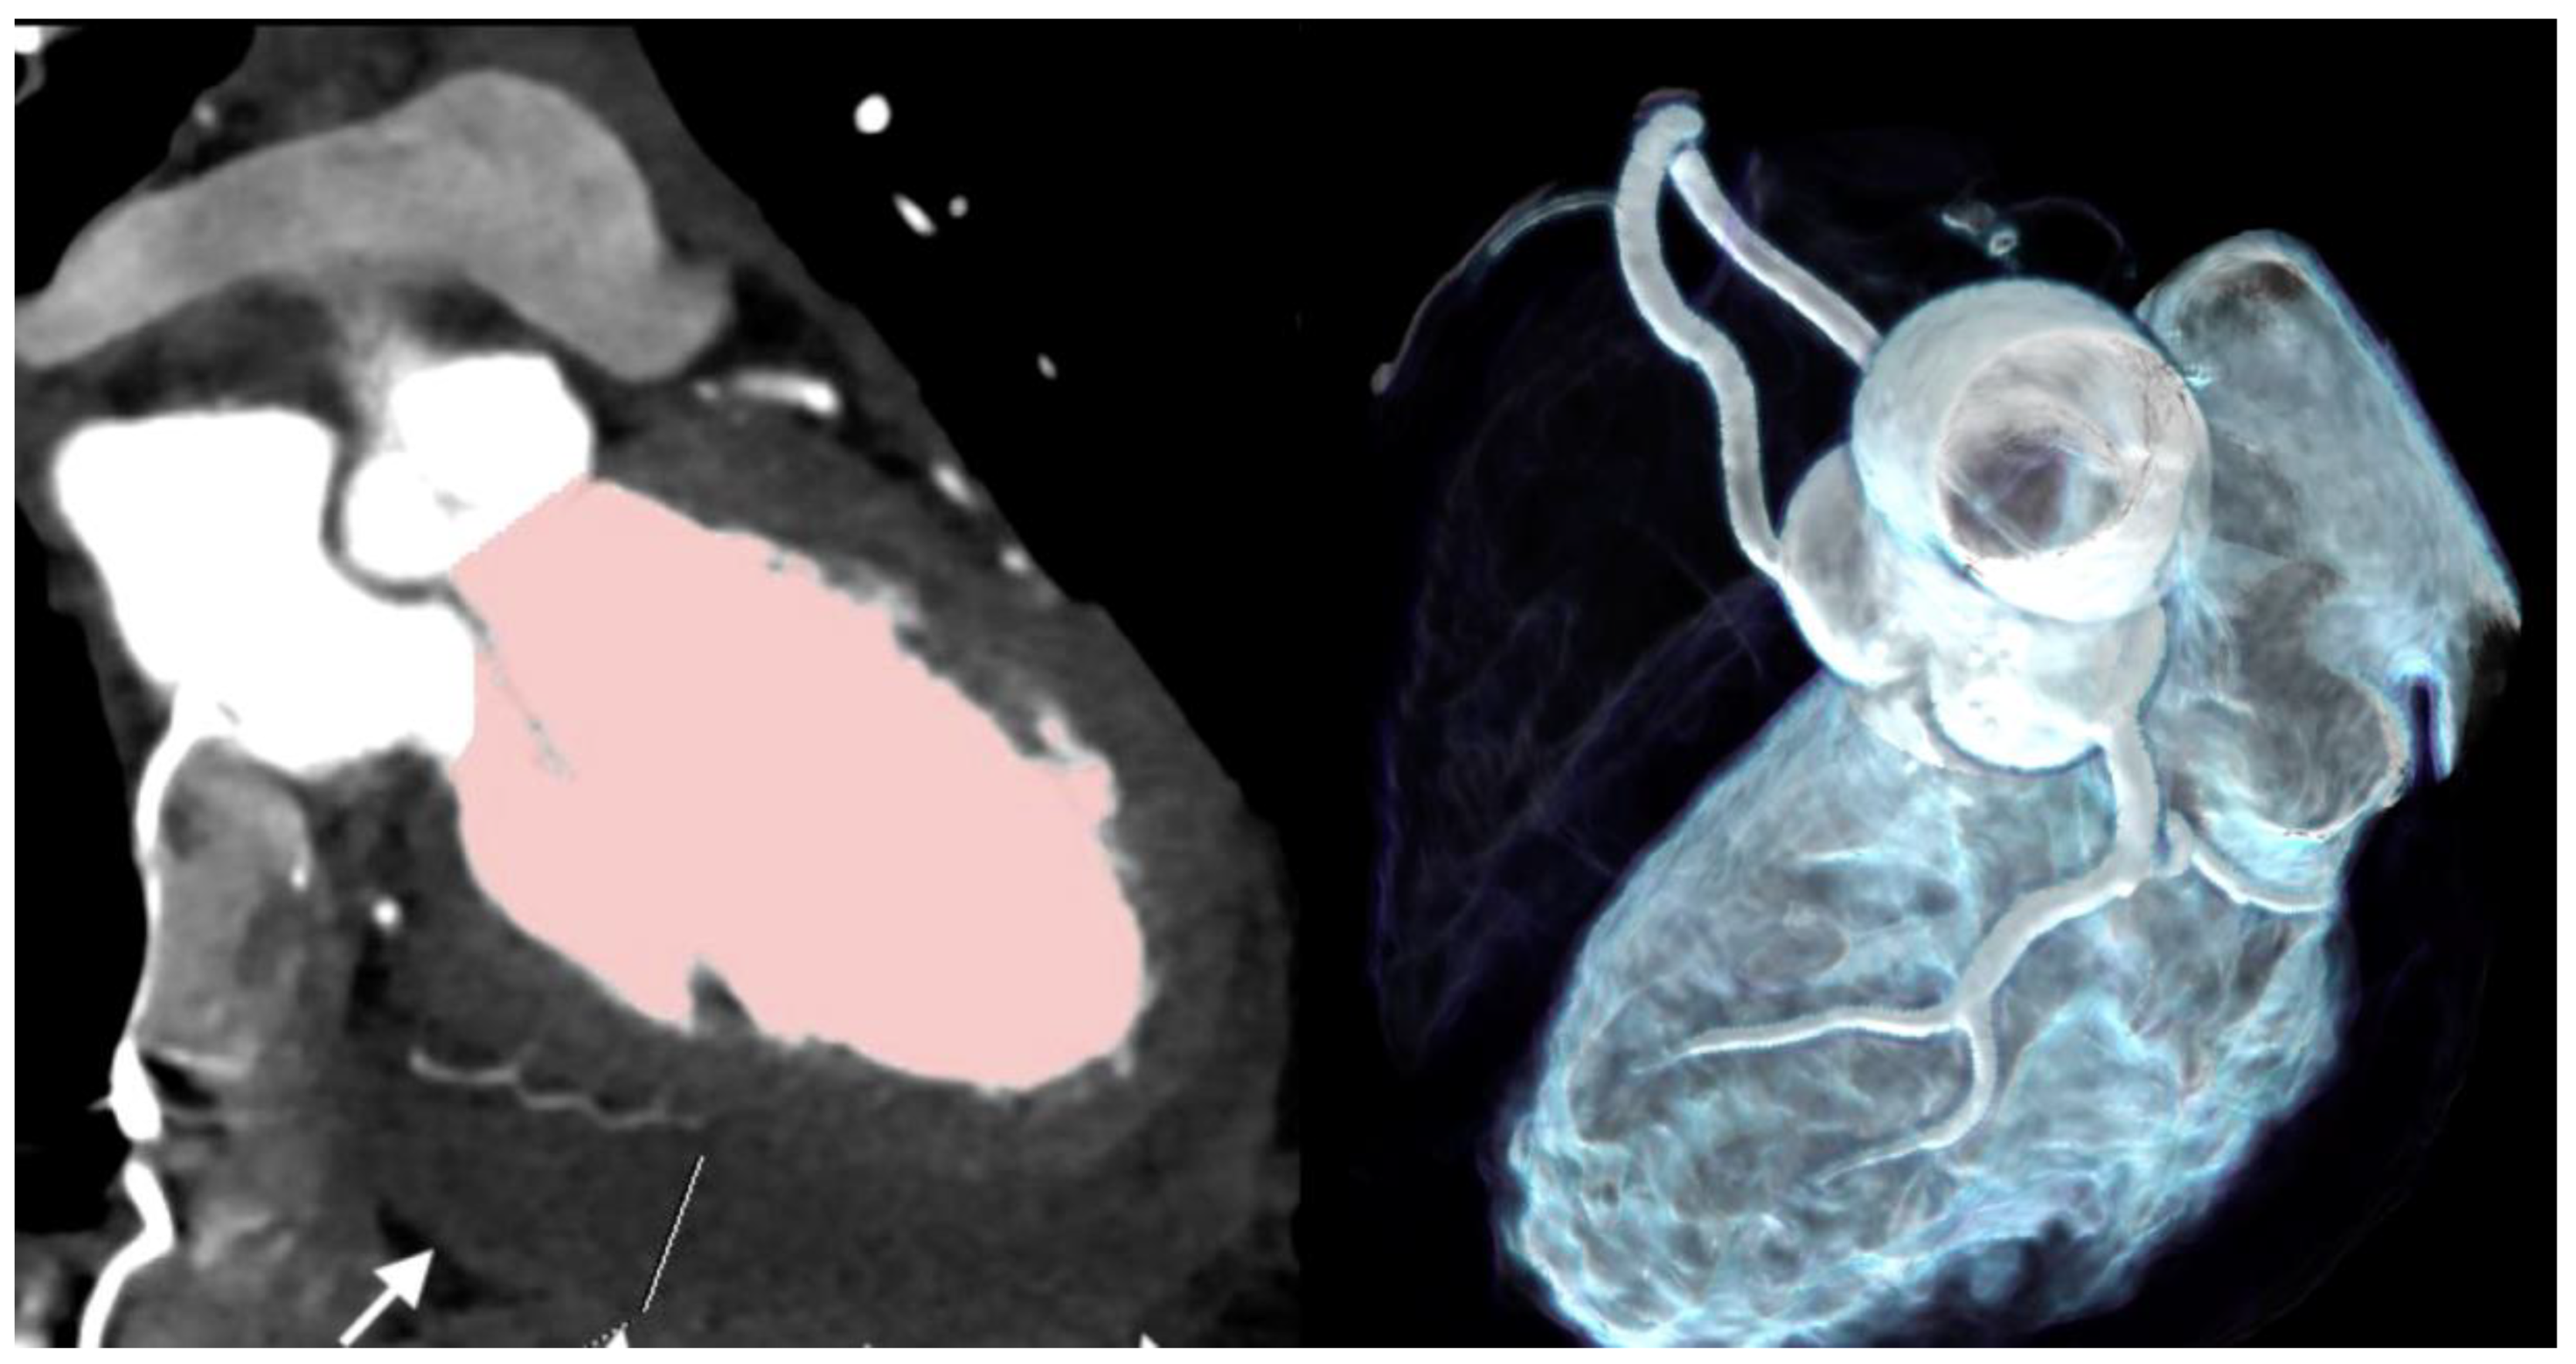

| Pericardial effusion | 4 (100%) | 2 (25%) |

| MINOCA | 2 (50%) | 0 (0%) |

| Hyperenhancing myocardium | 1 (25%) | 0 (0%) |

| Perivascular inflammation (PCAT+) | 4 (100%) | 2 (25%) |